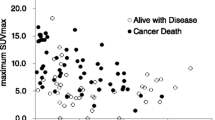

Correlation between tumour SUVmax and tumour size

The tumour SUVmax (range 1.8–20.7 and mean 5.0 ± 3.7 vs. range 1.8–19.0 and mean 4.5 ± 3.2 for observers 1 and 2, respectively) was moderately correlated with tumour size (r = 0.47, P = 0.0066 vs. r = 0.40, P = 0.024 for observers 1 and 2, respectively) (Fig. 4).

Correlation between SUV and pathological grade